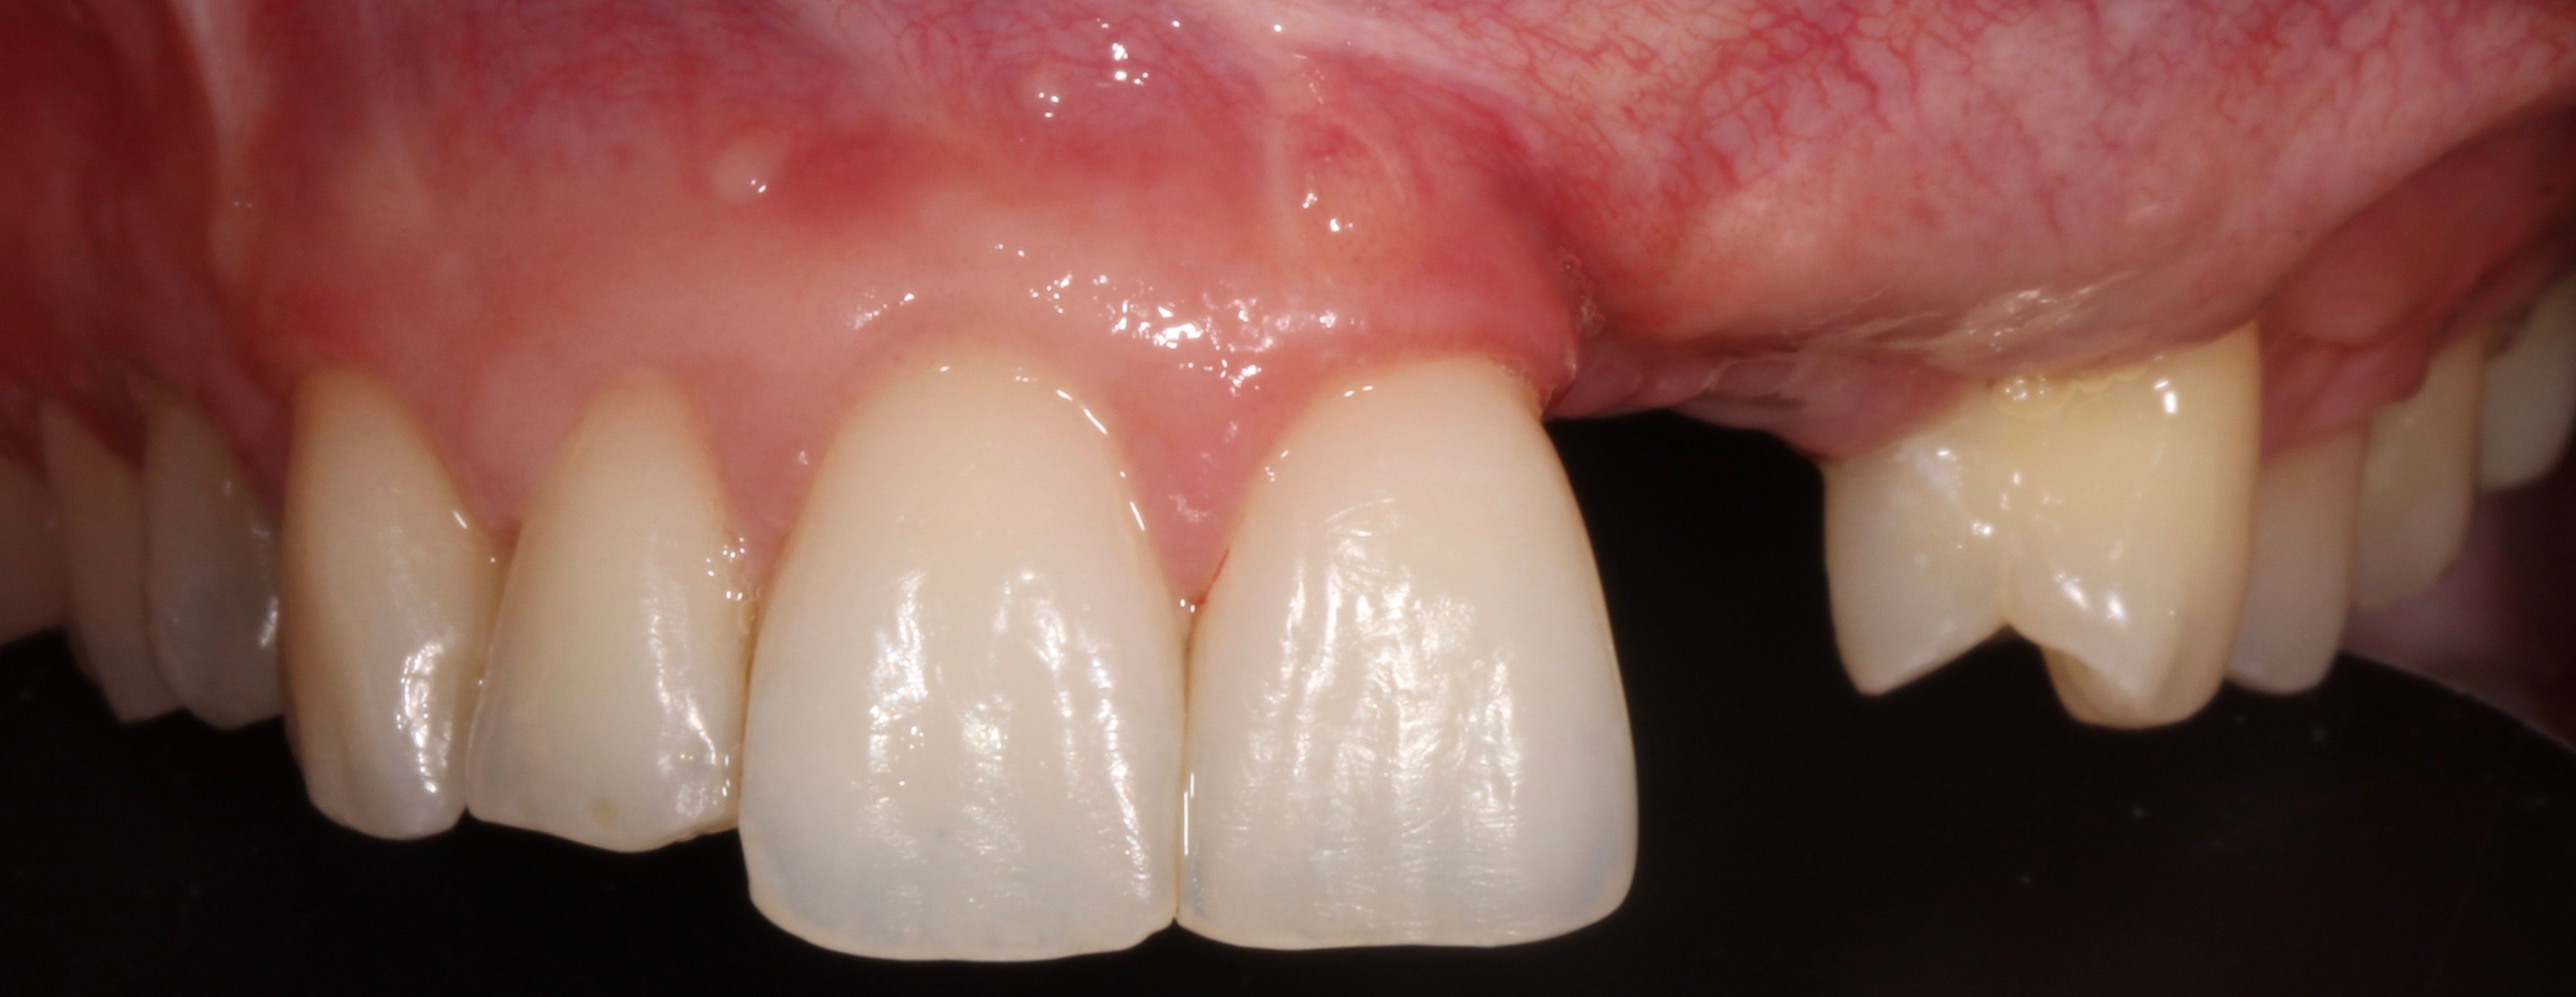

- 2 months later: 2nd surgical phase and temporary restoration.

- 2 years later: Final prosthesis.

- 4 years later: Clinical and Radiographic Evolution of the Aesthetic Zone.